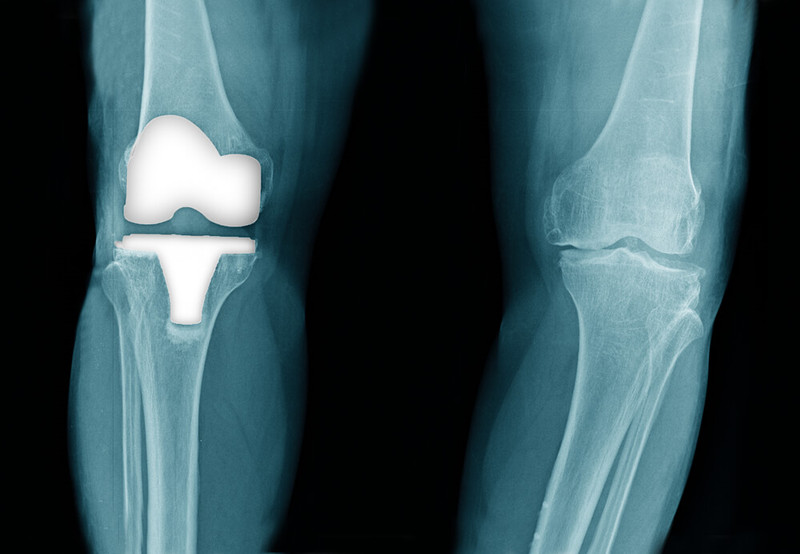

人工关节能用多少年?20年后是否还能用?由于每个患者的情况不同,选择的医院和医生也不同,一直没有明确的答案,2017年4版的医学杂志《柳叶刀》发表了一篇文章,研究人员发现:

- 在55000名进行膝关节置换的人中,3.9%的人需要在手术后10年内进行翻修手术,到20 年时,有10.3%需要翻修。

- 20年后没有出现植入失败。

这个结果说明人工膝关节比想象的使用时间要长,并且大部分患者没有感到不适。但也必须承认调查的范围比较小,只有128名患者,还需要更多的数据支撑。二次翻修手术主要是人工关节的使用寿命造成的,它主要包括以下几个原因: